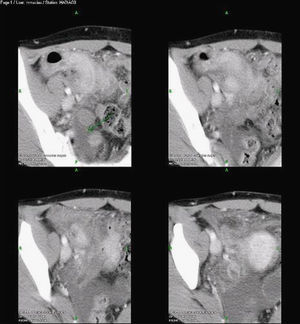

A la exploración, se encuentra un abdomen distendido, doloroso a la palpación en fosa iliaca derecha, dolor a la descompresión, signos apendiculares positivos (McBurney, Rovsing, Blumberg) y fiebre de 37,8°C. Se realizaron un tránsito intestinal, una ecosonografía y una TC abdominopélvica (fig. 1), donde se evidencian cambios inflamatorios en íleon distal y ciego. Se decide realizar una laparoscopia diagnóstica. Se encontró un apéndice vermiforme, con proceso inflamatorio severo, retrocólica, adherida firmemente a la pared abdominal, fibrosis intensa, eritema y múltiples abscesos, realizando una apendicectomía laparoscópica, sin necesidad de resección ileocólica. El estudio histopatológico reportó gránulos de sulfuro, microabscesos, fibrosis y infiltrado eosinofílico evidenciando la presencia de A. israelí (apendicitis crónica por actinomicosis) (fig. 2).

La actinomicosis es una patología insidiosa y de difícil diagnóstico, especialmente cuando la localización es abdominal8. Pocos médicos tienen presente este diagnóstico, por lo que suele pasar inadvertido y manifestarse crónicamente con las complicaciones tardías de la enfermedad. En 2003, Echenique et al describen, en la Revista Española de Enfermedades Digestivas, que el diagnóstico de actinomicosis abdominal se sospecha cuando en una TC se observan masas quísticas mal definidas, que presentan realce con contraste o formas de infiltración seudotumoral mesentérica. Mediante la TC o la ecografía se puede realizar una biopsia o un drenaje percutáneo dirigido, aunque el diagnóstico definitivo es el estudio histopatológico de la pieza quirúrgica.